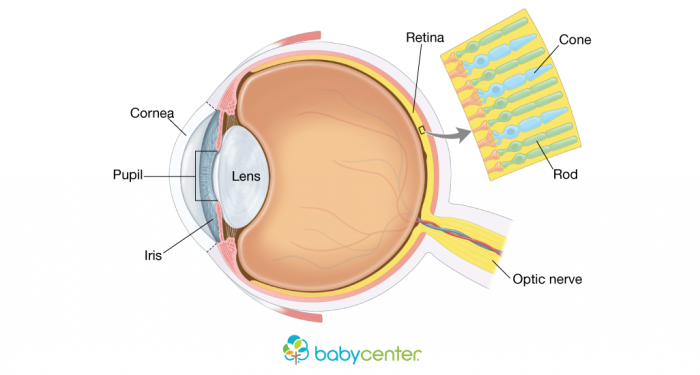

When a fetus is growing, the optic nerve is one of the first parts of the ocular system to start developing. During the fourth week of pregnancy, cells from the developing brain tissue start to form two optic nerves. Other cells also start developing into what will become the lens of the eye, which help babies focus on things both far and near.

“In the developing eye, perhaps 3% of ganglion cells — the cells in the retina that send messages through the optic nerve into the brain — are sensitive to light and, to date, researchers have found about six different subtypes that communicate with various places in the brain,” Science Daily explained.